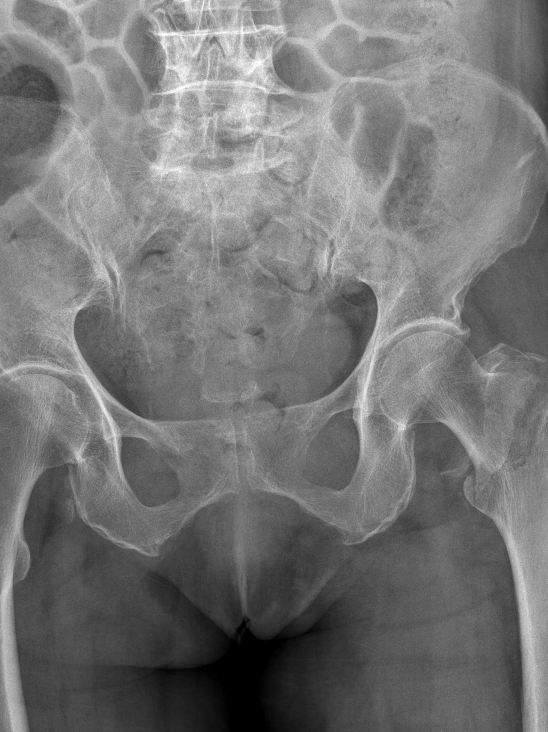

为提升区域内基层医疗机构糖尿病足诊疗服务能力、促进青年医师对糖尿病足的规范化诊治水平,遵义市第二城市医疗集团总院(贵州航天医院)圆满举办贵州省继续医学教育项目——胫骨横向骨搬移技术治疗糖尿病足专题研讨班。 贵州航天医院党委委员、副院长彭亮出席会议并致辞,遵义市第二城市医疗集团各成员单位,以及红花岗区、汇川区、绥阳县、桐梓县等多个区县的基层医疗机构骨干医师参加会议。 研讨班 本次研讨班以胫骨横向骨搬移技术在糖尿病足治疗中的应用为核心主题,围绕糖尿病药物治疗与生活方式管理策略、围手术期血糖精准调控要点、胫骨横向骨搬移技术典型病例深度解析、糖尿病足的临床分型与个体化治疗方案制定等临床实践中的热点与难点展开深入探讨,通过专题授课、案例研讨、互动交流等多元化形式,为参会者搭建了理论与实践结合的学习平台。 此次研讨班不仅为区域内基层医院搭建了学术交流与经验共享的平台,更对推动糖尿病足预防、诊断与治疗的规范化、系统化发展起到了积极作用,有效助力青年医师更新专业知识体系、提升临床技能,为进一步保障区域内糖尿病足患者的健康奠定了坚实基础。 贵州航天医院骨科专家简介 陈明勇 骨一科主任,副主任医师 临床擅长:从事创伤骨科工作约20年,对骨缺损、骨不连、骨肿瘤、肢体畸形等的肢体矫形重建及功能重建,慢性化脓性骨髓炎的根治治疗、糖尿病足的保肢治疗、快速康复理念(ERAS)下的老年骨折的诊治,四肢复杂骨折的诊治,四肢骨折等微创手术治疗具有丰富的临床经验。 2004年毕业于遵义医学院临床专业,曾在中国人民解放军总医院、广西医科大学第一附属医院、上海第六人民医院骨科进修。中国中西医结合学会骨伤科专业委员会横向骨搬移治疗糖尿病足及微血管网再生学组首届委员,遵义市医学会创伤分会常务委员。 瞿 晖 骨科党支部书记,骨二科主任,副主任医师 临床擅长:对骨科的常见病、关节外科、脊柱外科及运动医学疾病的诊治具有丰富的临床经验,熟练掌握骨科手术操作技术。 毕业于遵义医学院临床医学系,2005年前往广州中山大学第一附院骨显微医学部进修学习,2011年前往成都华西医院进修学习,并多次在省内外学习骨科相关知识,是中华医学会骨科分会会员。 赵小锋 中共党员,骨二科副主任,副主任医师 临床擅长:从事骨科临床工作11年,对骨科常见病、多发病诊疗有较为丰富的临床经验,擅长脊柱相关疾病诊断及治疗,尤其是颈、腰、腿疼痛疾病诊断及治疗,擅长胸腰椎骨折微创经皮穿刺内固定术、经皮穿刺椎体成形术、经皮穿刺脊柱内镜下腰椎间盘摘除术、单纯开创腰椎间盘摘除术、腰椎滑脱复位椎间植骨椎融合内固定术、腰椎管狭窄减压融合内固定术及人工髋、膝关节置换术等。 2012年毕业于遵义医学院外科学专业硕士研究生,2019年参加“遵义市115医学人才精英计划”于上海交通大学第一附属医院培训学习,2023年于北京大学第三人民医院脊柱外科进修学习,曾获得遵义市优秀医师荣誉称号。 遵义市手外科第一届委员,遵义市医学会创伤分会第一届委员,遵义市医学会创伤分会第二届委员,贵州省康复医学会第三届脊柱脊髓专业会委员,遵义市医学会烧伤与整形外科学分会委员,发表论文5篇,其中国家级核心期刊1篇,SCI论文1篇,主持市级课题1项并结题,参与市级课题2项。 赵兴东 骨科主任医师 临床擅长:擅长骨科的常见病及各种创伤、四肢骨折创伤修复、骨感染、手足疾病的诊治和手足体表畸形的矫形整复,熟练掌握骨科四肢骨病及创伤的手术操作技术,尤其在四肢关节复杂性损伤、手足外伤、组织缺损创面、难治创面的皮瓣修复方面及平足、高弓足矫形方面及四肢慢性疼痛诊治、康复方面具有丰富的临床经验。 硕士研究生,毕业于遵义医学院临床外科系,2015年前往山东省立医院手足外科进修学习;遵义市医学分会创伤分会第一、二届委员,遵义市手外科医学会第二委届员会常务委员;在省级及省级以上期刊发表文章9篇,参编著作2部,参与主持并完成市级课题1项,参与市级课题2项、省级课题1项。 张艳金 中共党员,骨科副主任医师 临床擅长:从事骨外科工作16年,对复合伤、多发伤的救治、四肢骨干骨折、关节周围骨折、骨肿瘤、骨髓炎等诊治具有丰富的临床经验。 中共党员,硕士研究生,2006年本科毕业于山西医科大学第二临床医学院,2011年研究生毕业于北京军区总医院;在“老年COPD患者合并髋部骨折的诊治”国际合作课题组研究两年,在老年髋部骨折的诊治方面具有丰富的经验,并发表论文6篇;主持遵义市级课题1项,承担遵义医科大学的临床教学工作,获得遵义医科大学优秀带教老师荣誉。编撰有《骨科疾病诊疗精粹》一书,开展2项新技术,编撰地方规范《务川自治县创伤骨科常见疾病诊疗规范》一书。 张俊凯 骨科副主任医师 临床擅长:从事骨科临床工作28年,对创伤骨折、骨感染、骨缺损、骨不连等外科诊治,四肢骨折的微创手术治疗,四肢复杂骨折(如关节内粉碎性骨折、多发骨折等)的损伤控制及手术治疗等具有丰富的临床经验。 1995年毕业于遵义医学院临床专业,2009年前往复旦大学附属医院骨科进修1年。 卢懿明 中共党员,骨科副主任医师 临床擅长:从事骨科工作18年,对创伤骨折、四肢骨折的微创手术治疗、四肢复杂骨折(如关节内粉碎性骨折、多发骨折等)的损伤控制及手术治疗,尤其是髋部骨折的PFNA等微创技术,踝关节骨折、膝关节周围骨折的Mipo微创技术等具有丰富的临床经验,开展了4项新技术,发明6项新型专利技术。 2005年毕业于遵义医学院临床专业,2017年,前往南方医科大学第三附属医院骨科进修半年,回院后运用Mipo技术对骨干骨折及干骺端骨折的治疗技术,同时积极开展骨盆骨折、髋臼骨折腹直肌外侧切口的应用;发表了多篇专业论文,经常参与省内外学术交流会授课,获得医院荣誉称号多个。 邬夏荣 骨科副主任医师 临床擅长:从事骨科工作16年,对四肢复杂骨折、骨肿瘤的诊治,尤其是足踝创伤、慢性踝关节损伤、平足症等诊疗具有丰富的临床经验。 2006年毕业于遵义医科大学临床医学专业,曾在陆军军医大学西南医院进修学习,发表多篇骨科学术论文。 余德怀 中共党员,骨科副主任医师 临床擅长:从事骨科工作10余年,对运动医学、骨关节、脊柱外科常见病、多发病的诊治具有丰富的临床经验。 硕士研究生,2011年毕业于遵义医学院临床医学专业,曾前往遵义医科大学附属医院运动医学专业进修学习;是贵州省医学会运动医学分会青年委员,西部关节镜联盟委员;发表多篇骨科学术论文。 冯 乾 骨科副主任医师 临床擅长:从事骨科工作近20年,熟练掌握骨科多发病及常见病的诊治,尤其对脊柱退变性疾病的诊断及治疗具有丰富的临床经验,主要研究脊柱微创相关治疗方式,能熟练开展椎间孔镜及UBE。 曾前往北京大学第三医院进修学习疼痛及椎间孔镜、首都医科大学友谊医院专业进修脊柱内镜;是贵州省康复医学会第三届脊柱脊髓专业委员会委员;发明专利3项、发表脊柱外科专业论文多篇。 贵州航天医院骨科简介 基本情况 贵州航天医院(原3417医院)骨科组建于1968年,前身是以创伤和断肢(断指)再植闻名于世的上海市第六人民医院骨科,中国断肢(断指)再植的奠基者、中科院院士陈仲伟等专家莅临科室指导医疗和教学,并在70年代开展了贵州省首例断肢(断指)再植手术。组建50余年来,诊治患者已逾百万,挽救了无数的伤病员,成为了保障遵义地区人民群众健康的重要支撑。 经过几代人的不懈努力,今天的骨科,已由创伤骨科发展至骨病、骨肿瘤、骨结核等领域,现有脊柱外科、关节外科、四肢创伤、手足外科四个亚专科,成为了集医疗、教学、科研于一体的综合学科,是贵州省临床重点专科、遵义市临床重点专科、遵义市骨科临床医学中心、遵义市基层骨科专科联盟理事长单位。 科室目前开放床位110张,共有医护人员50余人,副高级以上专家18人,硕士研究生15人。拥有一流骨科医疗设备多台,每年不定期选派优秀技术骨干到全国各大知名医学院校进修、学习、参观、交流,并邀请国内、国外知名专家教授来院进行交流、指导,通过不断引进国内外先进的诊疗技术,科室医疗技术水平稳步提升,为广大人民群众提供了优质的医疗服务。 专科特色 骨一科 (一)骨缺损、骨不连的肢体与功能重建 胫骨横向骨搬移技术治疗糖尿病足: (二)慢性骨髓炎的根治治疗 (三)肢体缺血性疾病如糖尿病足、脉管炎的保肢治疗 (四)皮瓣修复 (五)复杂创伤的治疗 (六)老年髋部骨折及小儿骨折快速手术 老年髋部骨折: 骨二科 (一)胸腰椎骨折微创经皮椎弓根螺钉固定术 (二)老年性骨质疏松性患者腰椎滑脱脊柱内固定术(骨水泥螺钉) (三)V形双通道脊柱内镜技术(VBE)腰椎融合术治疗腰椎退行性疾病 (四)老年性骨质疏松性骨折(PVP/PKP)术 (五)人工髋关节置换术 (六)双侧股骨头坏死人工全髋关节置换 (七)右侧全髋置换术后假体周围骨折翻修 (八)人工膝关节置换术 (九)人工膝关节假体松动翻修 (十)关节镜技术 传统手术切口 关节镜技术切口 诊疗范围 骨一科 1.四肢创伤、矫形。 2.手、足踝外科。 骨二科 End